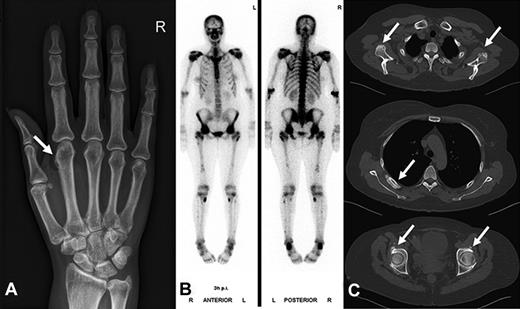

Radiographic findings and bone scintigraphy in patient 2. (A) Plain film showing marked periosteal bone apposition on radial and distal diaphysis of the first metacarpal bone of the right hand (arrow). (B) Technetium 99m-methyl-diphosphonate bone scintigraphy showing marked tracer uptake in the entire skeleton, most pronounced in the spine and pelvis. There are active spots in bones of both hands and feet. (C) CT scan of the entire skeleton revealed bone appositions in various sites of the skeleton (arrows): at the caudal margin of the glenoid (top), at the dorsal ribs (middle), and periacetabular on both sides (bottom). Findings are typical of hypertrophic osteoarthropathy.